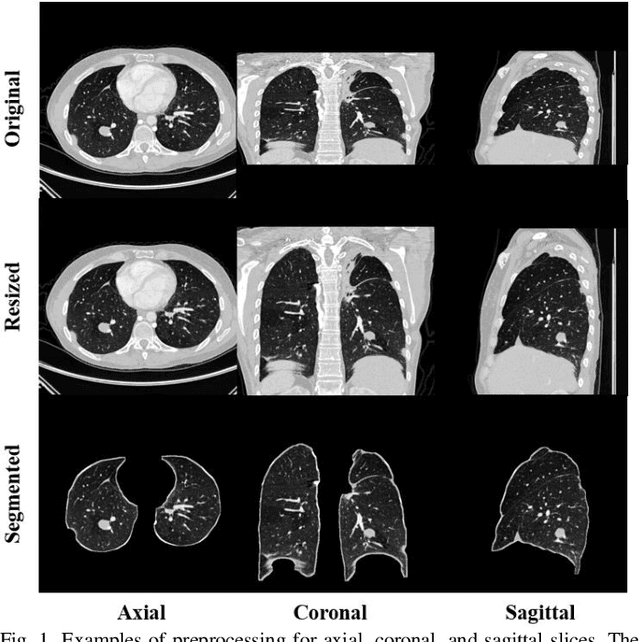

Abstract:We propose a multi-planar pulmonary nodule detection system using convolutional neural networks. The 2-D convolutional neural network model, U-net++, was trained by axial, coronal, and sagittal slices for the candidate detection task. All possible nodule candidates from the three different planes are combined. For false positive reduction, we apply 3-D multi-scale dense convolutional neural networks to efficiently remove false positive candidates. We use the public LIDC-IDRI dataset which includes 888 CT scans with 1186 nodules annotated by four radiologists. After ten-fold cross-validation, our proposed system achieves a sensitivity of 95.3% with 0.5 false positive/scan and a sensitivity of 96.2% with 1.0 false positive/scan. Although it is difficult to detect small nodules (i.e. nodules with a diameter < 6 mm), our designed CAD system reaches a sensitivity of 93.8% (94.6%) of these small nodules at an overall false positive rate of 0.5 (1.0) false positives/scan. At the nodule candidate detection stage, the proposed system detected 98.1% of nodules after merging the predictions from all three planes. Using only the 1 mm axial slices resulted in the detection of 91.1% of nodules, which is better than that of utilizing solely the coronal or sagittal slices. The results show that a multi-planar method is capable to detect more nodules compared to using a single plane. Our approach achieves state-of-the-art performance on this dataset, which demonstrates the effectiveness and efficiency of our developed CAD system for lung nodule detection.